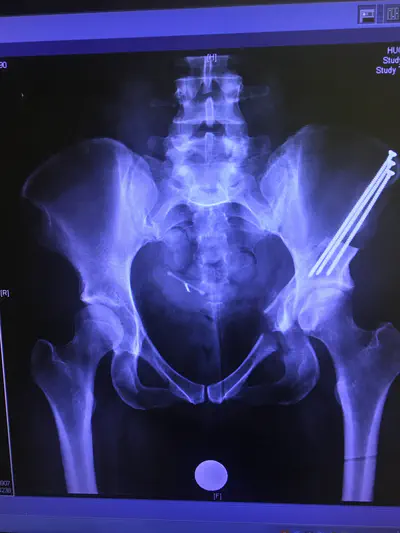

One of the things that happens to you, I guess, when you have a connective tissue disorder, is your bones don’t form right. I have dysplasia in both my hips, and in 2017 I had a procedure (periacetabular osteotomy, or PAO) to correct it on one side. They cut my pelvis in three places, removing the hip socket from the rest of my pelvis, which they then reoriented it and screwed back in place with three five-inch screws that are still inside me.

my actual hip